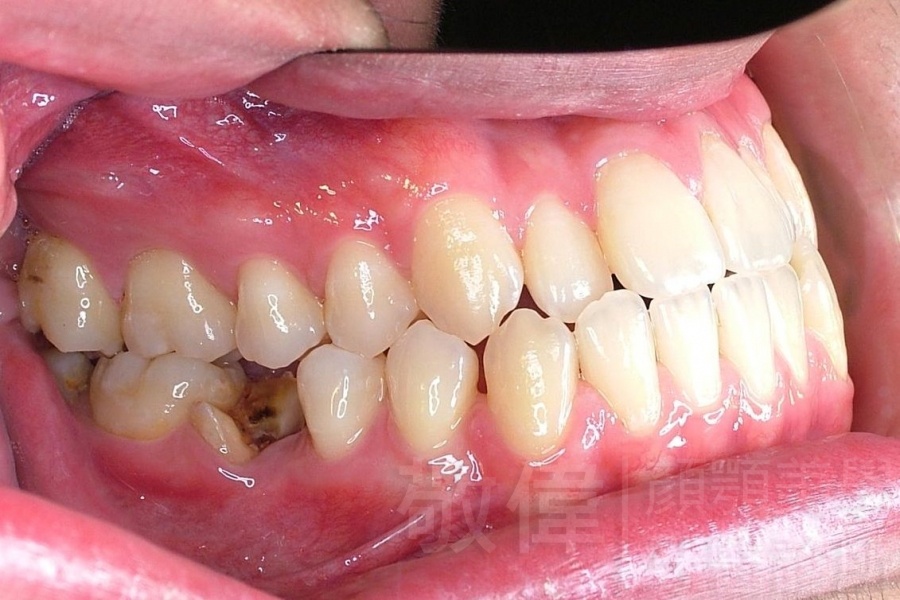

齒顏矯正/戽斗、亂牙、爛牙,變身 免植牙的健牙美女

變臉矯正,原來戽斗妹跟大歪臉變成自信正妹

經由本院3D數影X光影像儀分析、與3D齒顎顏矯正技術,再配合口腔顎面正顎專科醫師施以正顎手術治療,雙方共同合作,使患者臉部外觀有很好的改善,大歪變小歪,產生了天南地北的大改變,她的人生也整個變得不一樣。

因為矯正與正顎手術的配合,使「戽斗妹」變成了「陽光正妹」,完全的改變了她的人生,在面對各種場合、與人交際都散發出自信微笑。所以,奉勸家長,如果小朋友有臉顎畸型的問題,應該考慮配合做這種簡單、安全、有效的正顎手術。